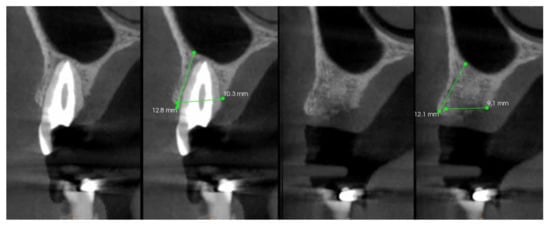

Each patient received two measurements in millimeters on CBCT0 and CBCT1: alveolar bone width (ABW), measured as distance between the most coronal point on the vestibular cortical bone and the most coronal point on the palatal cortical bone; and alveolar bone height (ABH), measured as the most coronal point on the vestibular cortical bone and the cortical bone of the maxillary sinus (Figure 4). The alveolar bone width reduction (ABWR) after four months was measured as a subtraction between ABW measured on CBCT0 and ABW measured on CBCT1. The alveolar bone height reduction (ABHR) after four months was measured as a subtraction between ABH measured on CBCT0 and ABH measured on CBCT1.

Figure 4. Measurements performed on the CBCT0 and CBCT1: alveolar bone width (ABW) and alveolar bone height (ABH).